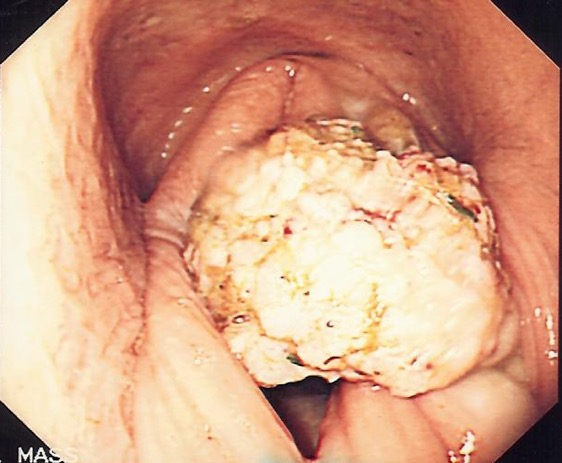

What does this image show (URT dx)?

Neoplasia